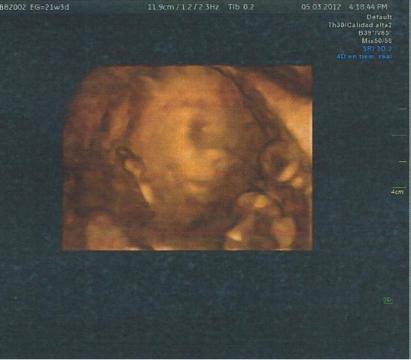

Pro větší náhled klikněte na obrázek

Je mi 37 let a jsem ve 23 týdnu a bolesti v krízi mi pomalu zacali uz ve 2 mesíci, ted je to ale cím dál tím horsí. Kdyz se snazím otocit v posteli je nemozné a kdyz vstanu a snazim se chodit na pravé strane dole to silne zabolí. Asi tretí den uz me bolí i pravá kycel, spávám nyní jen na levé strane a mezi koleny mám polstár ale i tak pravá kycel zlobí. Nevím co mám delat, cvicení odkládám, mám strach se nejak jinak pohnout. Nekdy to rozchodím kdyz vstanu a hned silne naslapuji na pravou nohu.